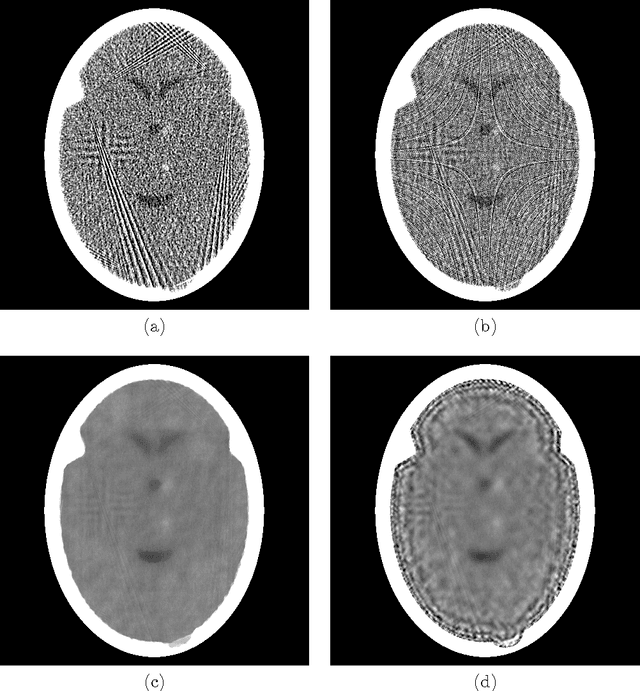

Abstract:To reduce the x-ray dose in computerized tomography (CT), many constrained optimization approaches have been proposed aiming at minimizing a regularizing function that measures lack of consistency with some prior knowledge about the object that is being imaged, subject to a (predetermined) level of consistency with the detected attenuation of x-rays. Proponents of the shearlet transform in the regularizing function claim that the reconstructions so obtained are better than those produced using TV for texture preservation (but may be worse for noise reduction). In this paper we report results related to this claim. In our reported experiments using simulated CT data collection of the head, reconstructions whose shearlet transform has a small $\ell_1$-norm are not more efficacious than reconstructions that have a small TV value. Our experiments for making such comparisons use the recently-developed superiorization methodology for both regularizing functions. Superiorization is an automated procedure for turning an iterative algorithm for producing images that satisfy a primary criterion (such as consistency with the observed measurements) into its superiorized version that will produce results that, according to the primary criterion are as good as those produced by the original algorithm, but in addition are superior to them according to a secondary (regularizing) criterion. The method presented for superiorization involving the $\ell_1$-norm of the shearlet transform is novel and is quite general: It can be used for any regularizing function that is defined as the $\ell_1$-norm of a transform specified by the application of a matrix. Because in the previous literature the split Bregman algorithm is used for similar purposes, a section is included comparing the results of the superiorization algorithm with the split Bregman algorithm.